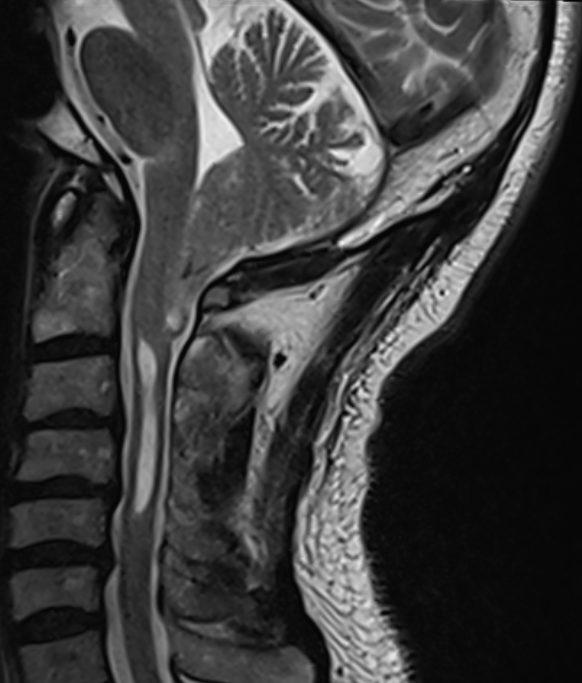

Chiari I Malformation MRI

Sagittale T2 Sequenz eines MRI von einem Patienten mit einer Chiari I Malformation und assoziierter Syringomyelie im Bereich der Halswirbelsäule.